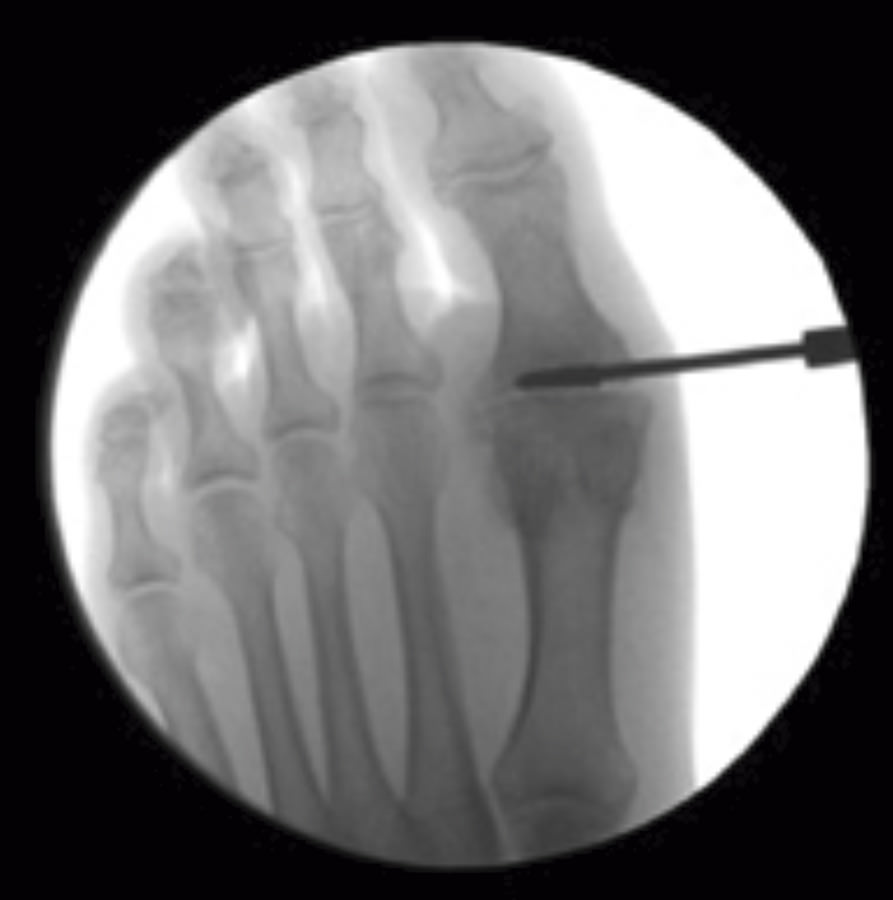

Se debe acceder a la articulación mediante 1 o 2 portales articulares situados a ambos extremos de la articulación a nivel dorsal (Figura 1). Deben ser unos portales un poco más grandes de lo normal, de 2 a 3 mm, que nos permitan un buen acceso a la articulación y poder extraer los fragmentos de cartílago que no podamos triturar. La fresa a utilizar es la Shannon® larga o Shannon® 44, que permite acceder a toda la articulación (Figura 2). En ocasiones, podemos utilizar la fresa de tipo pino (llamada así por su forma).

Figura 1. Portal articular a través del cual la fresa Shannon® elimina el cartílago y prepara las superficies articulares.

La posición de la artrodesis se determina utilizando la proyección de perfil con el Fluoroscan®, para evitar subluxaciones de la misma. Es con la visión de perfil cuando se colocan las agujas de Kirschner para los tornillos canulados y, después, se comprueba que la posición es correcta con la visión de frente. De forma percutánea, se colocan 2 agujas de Kirschner, una desde la primera falange y otra desde el metatarsiano en forma de X, cruzándose al nivel de la articulación (Figura 4). Es útil comprimir los dos huesos con la mano mientras se pasan las agujas.

Figura 4. Los 3 portales necesarios para la artrodesis percutánea de la articulación metatarsofalángica del primer dedo. El portal más proximal y el más distal se utilizan para la introducción de los tornillos canulados.